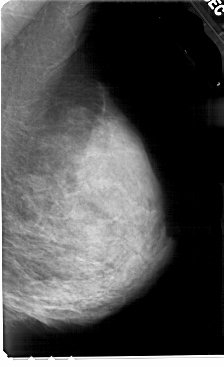

A_1678_1.RIGHT_MLO

RIGHT_MLO LINES 5491 PIXELS_PER_LINE 3346 BITS_PER_PIXEL 12 RESOLUTION 43.5 NON_OVERLAY